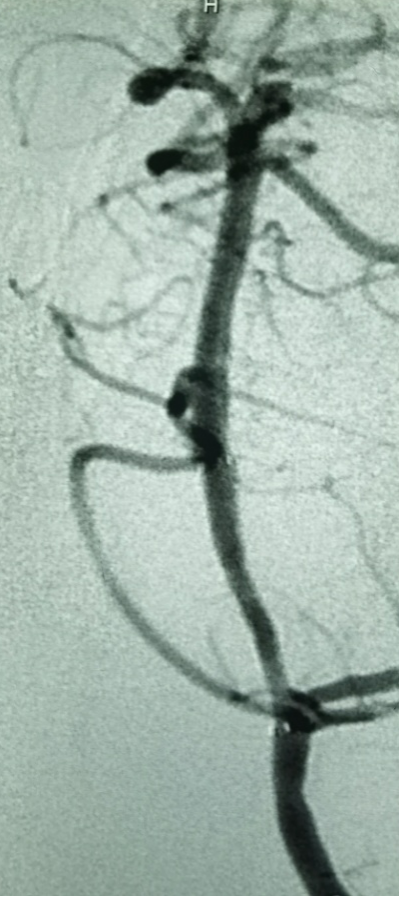

引入加奇SacSpeed® 2.0mm×12mm颅内球囊扩张。

扩张后造影,提示恢复正向血流,残余狭窄50%左右。

换用加奇SacSpeed® 2.5mm×12mm颅内球囊扩张。

扩张后造影提示,正向血流理想,闭塞节段成型理想。